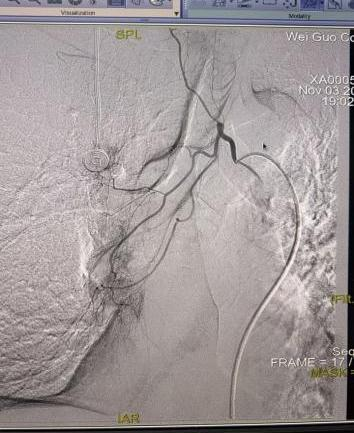

案例二:魏先生,64岁,肾恶性肿瘤术后肝、肺转移。2025年11月3日,在DSA引导及局麻下行经导管支气管动脉联合肝动脉造影、栓塞+灌注化疗术,实现多部位协同治疗。

支气管动脉造影                                                                    肝动脉造影